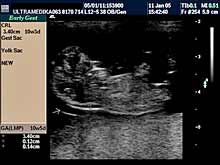

A) I trimestar do 14

nedelje gestacije

(3 meseca + 2 nedelje)

Indikacije za ultrazvučni pregled:

- Izostanak menstruacije, procena vitalnosti rane trudnoće,

procena materične i/ili postojanje vanmaterične trudnoće.

(Od 4-7 nedelje gestacije, ili prva 2 meseca od prvog dana zadnje

menstruacije).